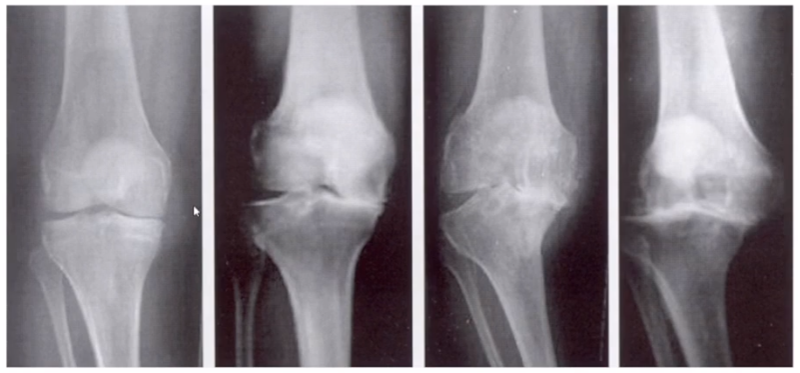

三、单髁置换的适应证——标准侧位片

标准侧位片,内外髁完全重叠,胫骨平台也一样,如果检查不标准,X线片结果会影响判断。

侧位片可以显示胫骨平台磨损部位,在判断前交叉韧带功能是否完好方面有重要意义。当磨损部位在前方或中前方,没有延伸到胫骨平台后缘时,说明前交叉韧带功能正常;当磨损部位延伸到胫骨平台后方,甚至引起后方半脱位状态时,说明前交叉韧带功能缺失或损害,此时不适合做单髁。

AMOA的侧位X线表现

ACL功能完好是单髁重要的适应证。当ACL失去功能,导致后方软骨磨损或者骨缺损,此时为整个内侧或全间室的骨关节炎,不是单髁的适应证了。

在牛津单髁标准教程里,表明前交叉韧带与后交叉韧带都应该保持功能正常,才是单髁的适应证。